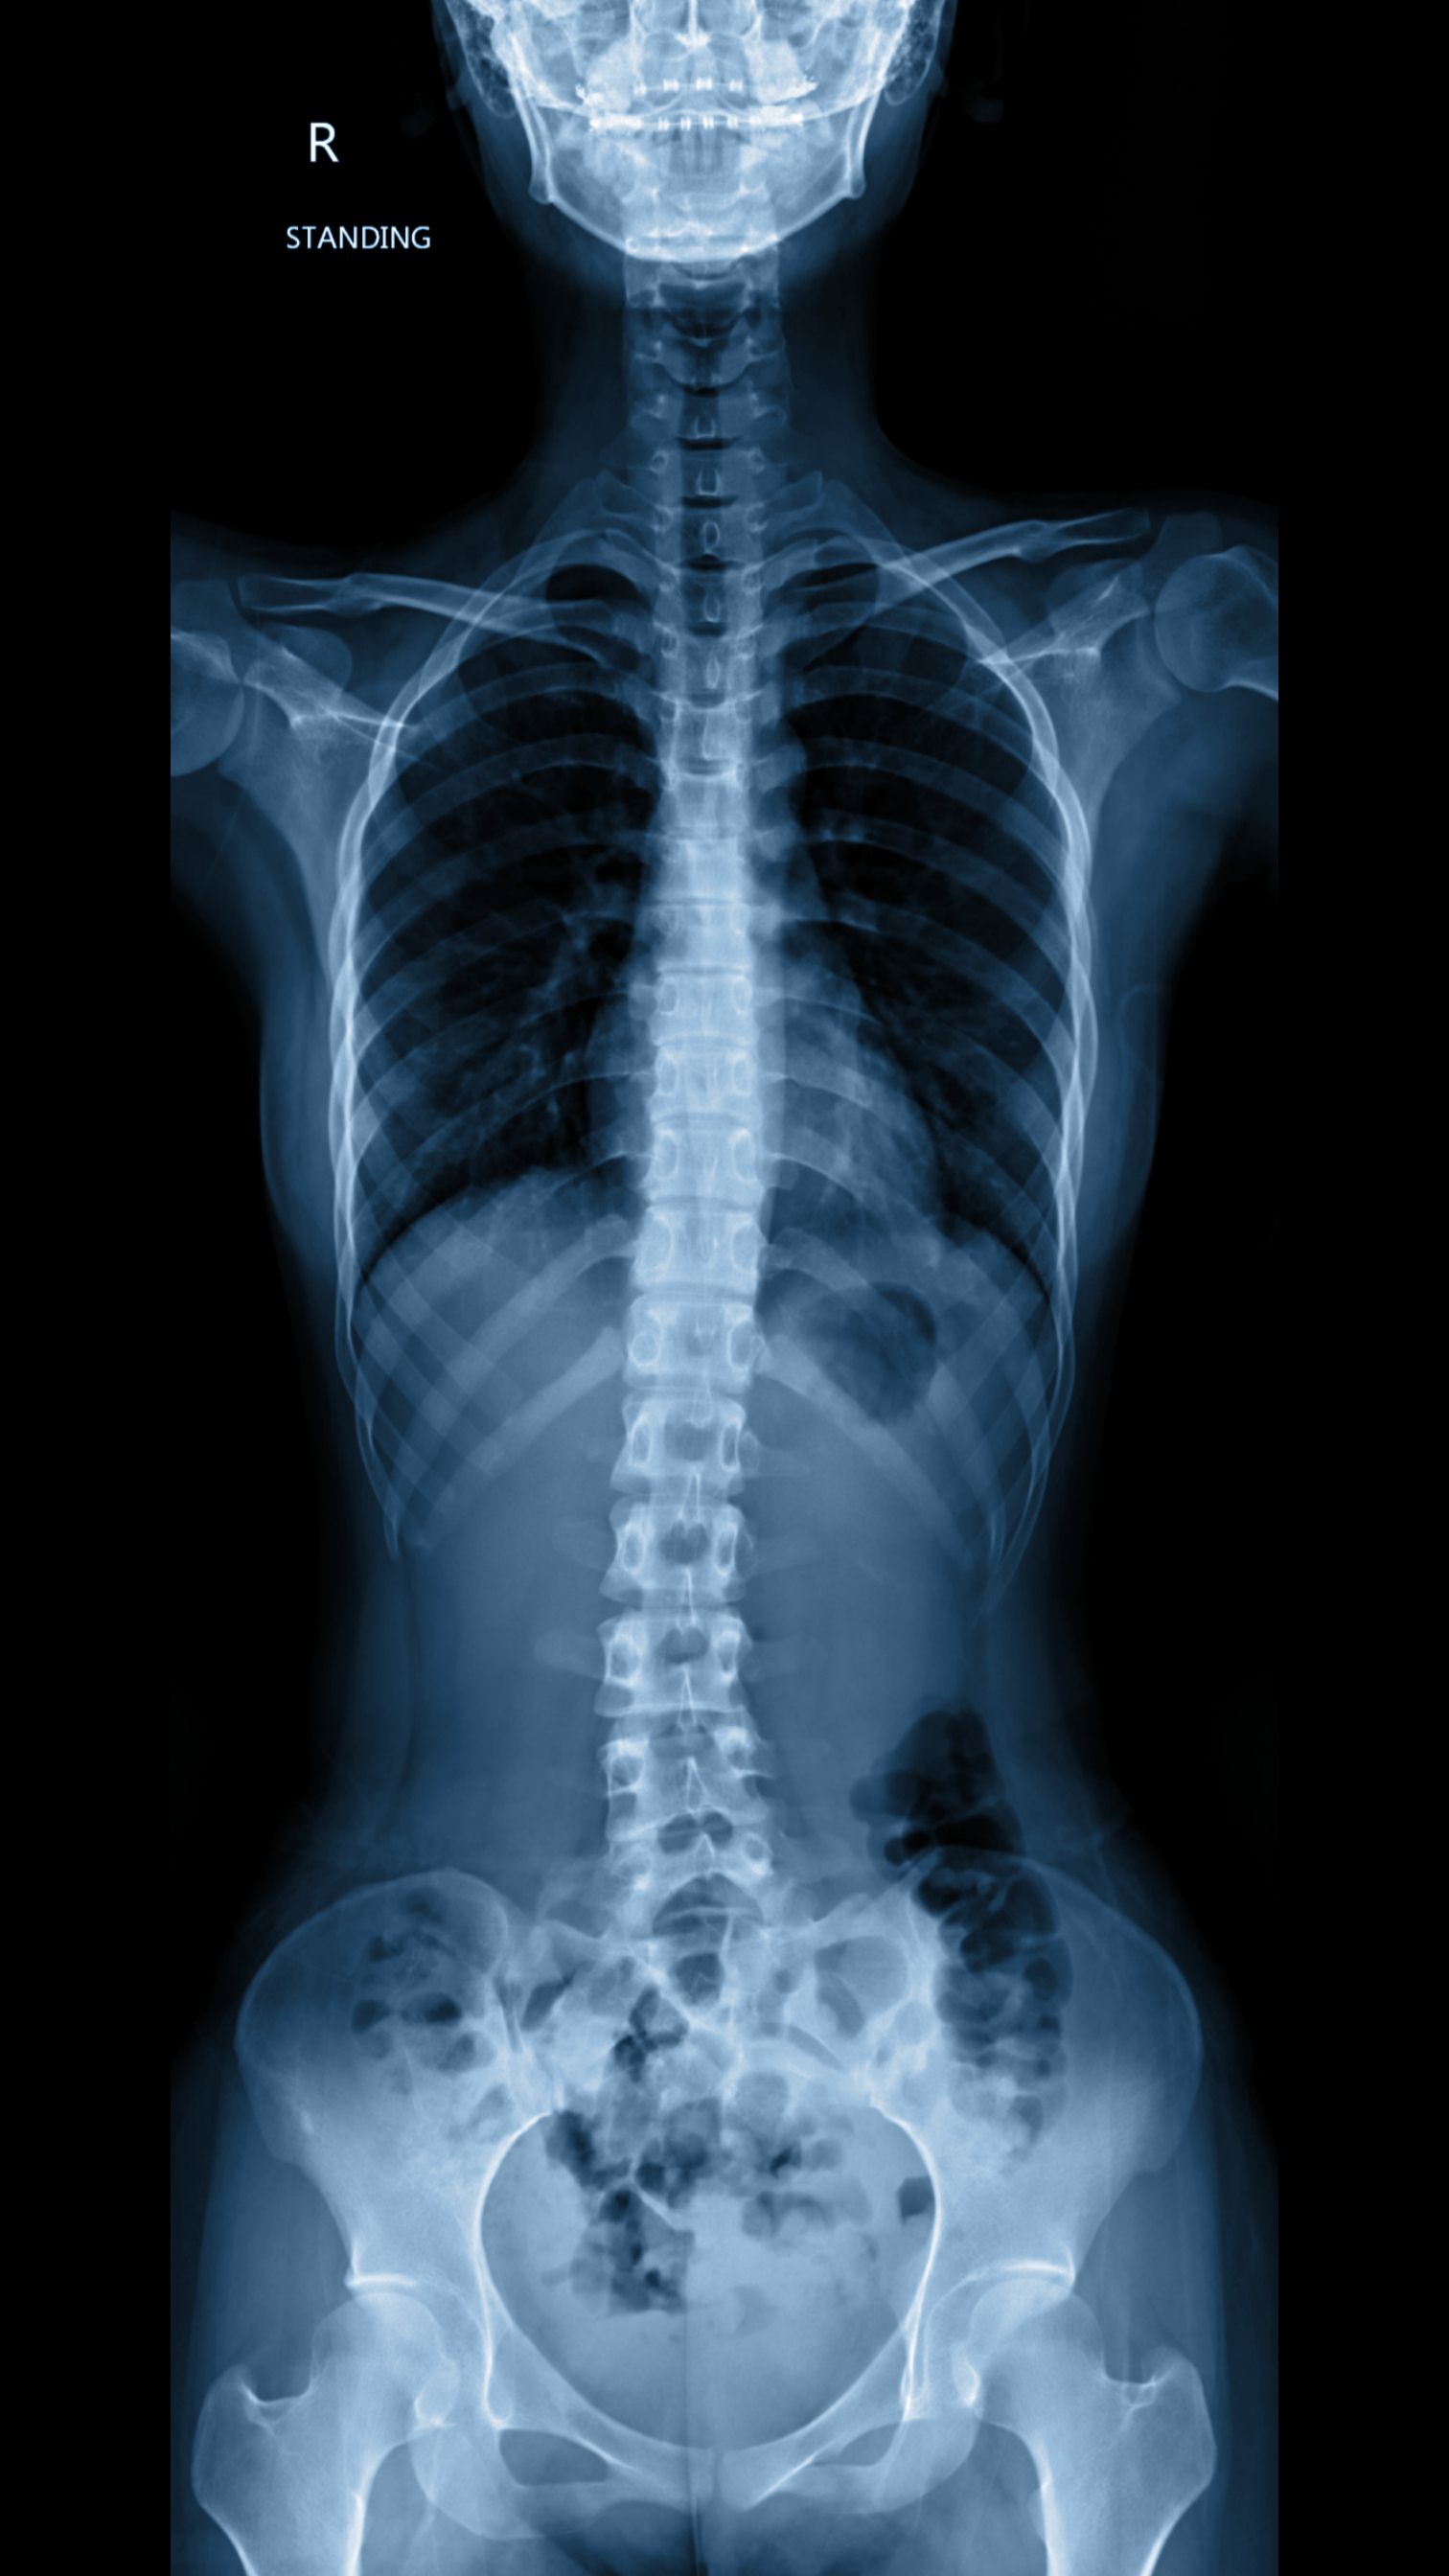

At the core of Chiropractic Biophysics® is the understanding that proper spinal alignment is crucial for optimal nervous system function. Misalignments, or subluxations, can interfere with nerve signals, leading to pain and dysfunction. CBP uses a combination of X-rays, postural analysis, and digital imaging to accurately diagnose these issues.